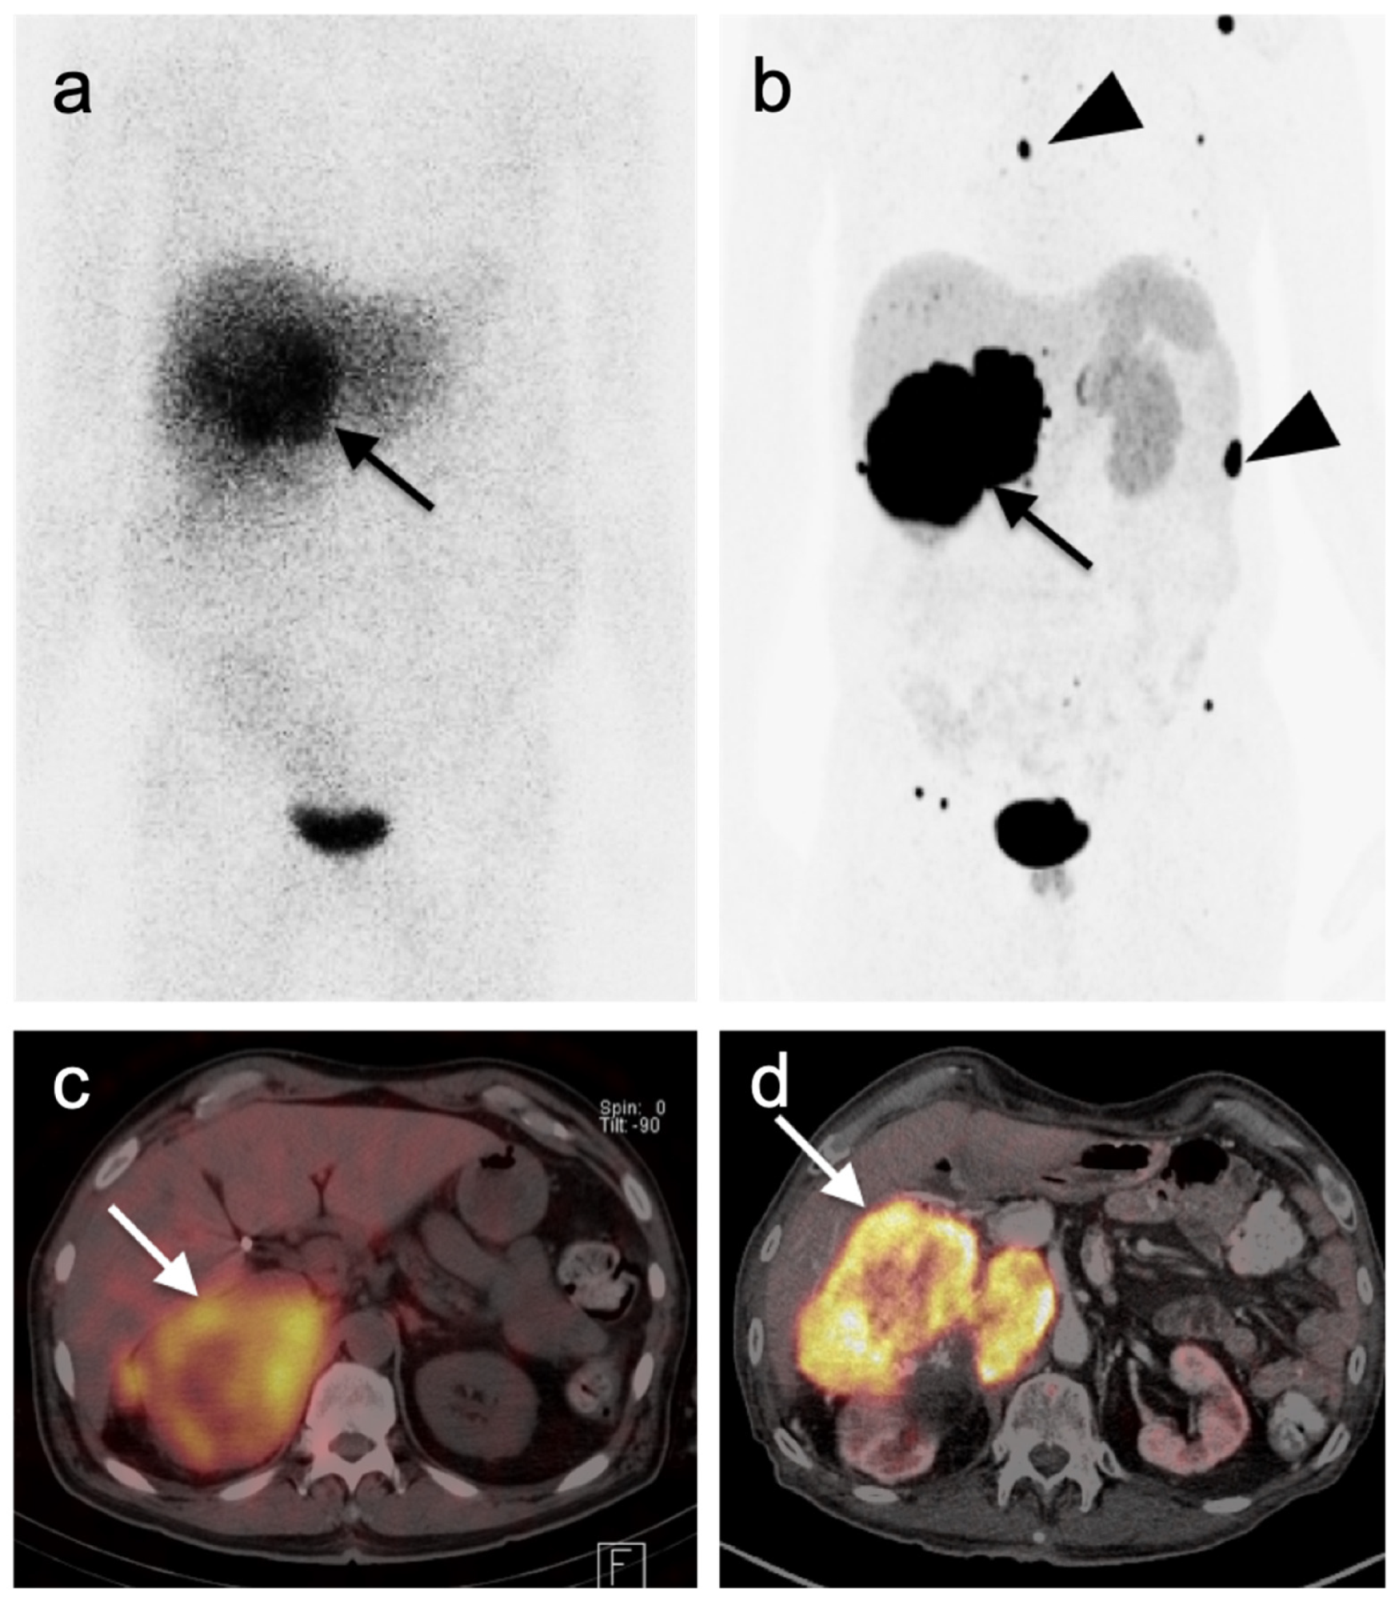

4.5. Pheochromocytoma and Paraganglioma